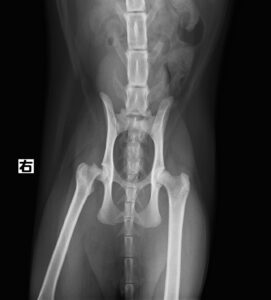

【整形外科】 右大腿骨頭すべり症

ジャンプした拍子に右後肢跛行とのことでかかりつけ医を受診後、セカンドオピニオンとして当院の整形外科に来院されました。若い雄猫に多く見られる「大腿骨頭すべり症」と診断。ご家族様と相談の上、骨頭切除を実施しました。経過は順調でしたが、その6ヶ月後に逆側も同様に骨折し、同治療を行いました。結果的に両側の骨頭切除が行われましたが、経過は良好です。